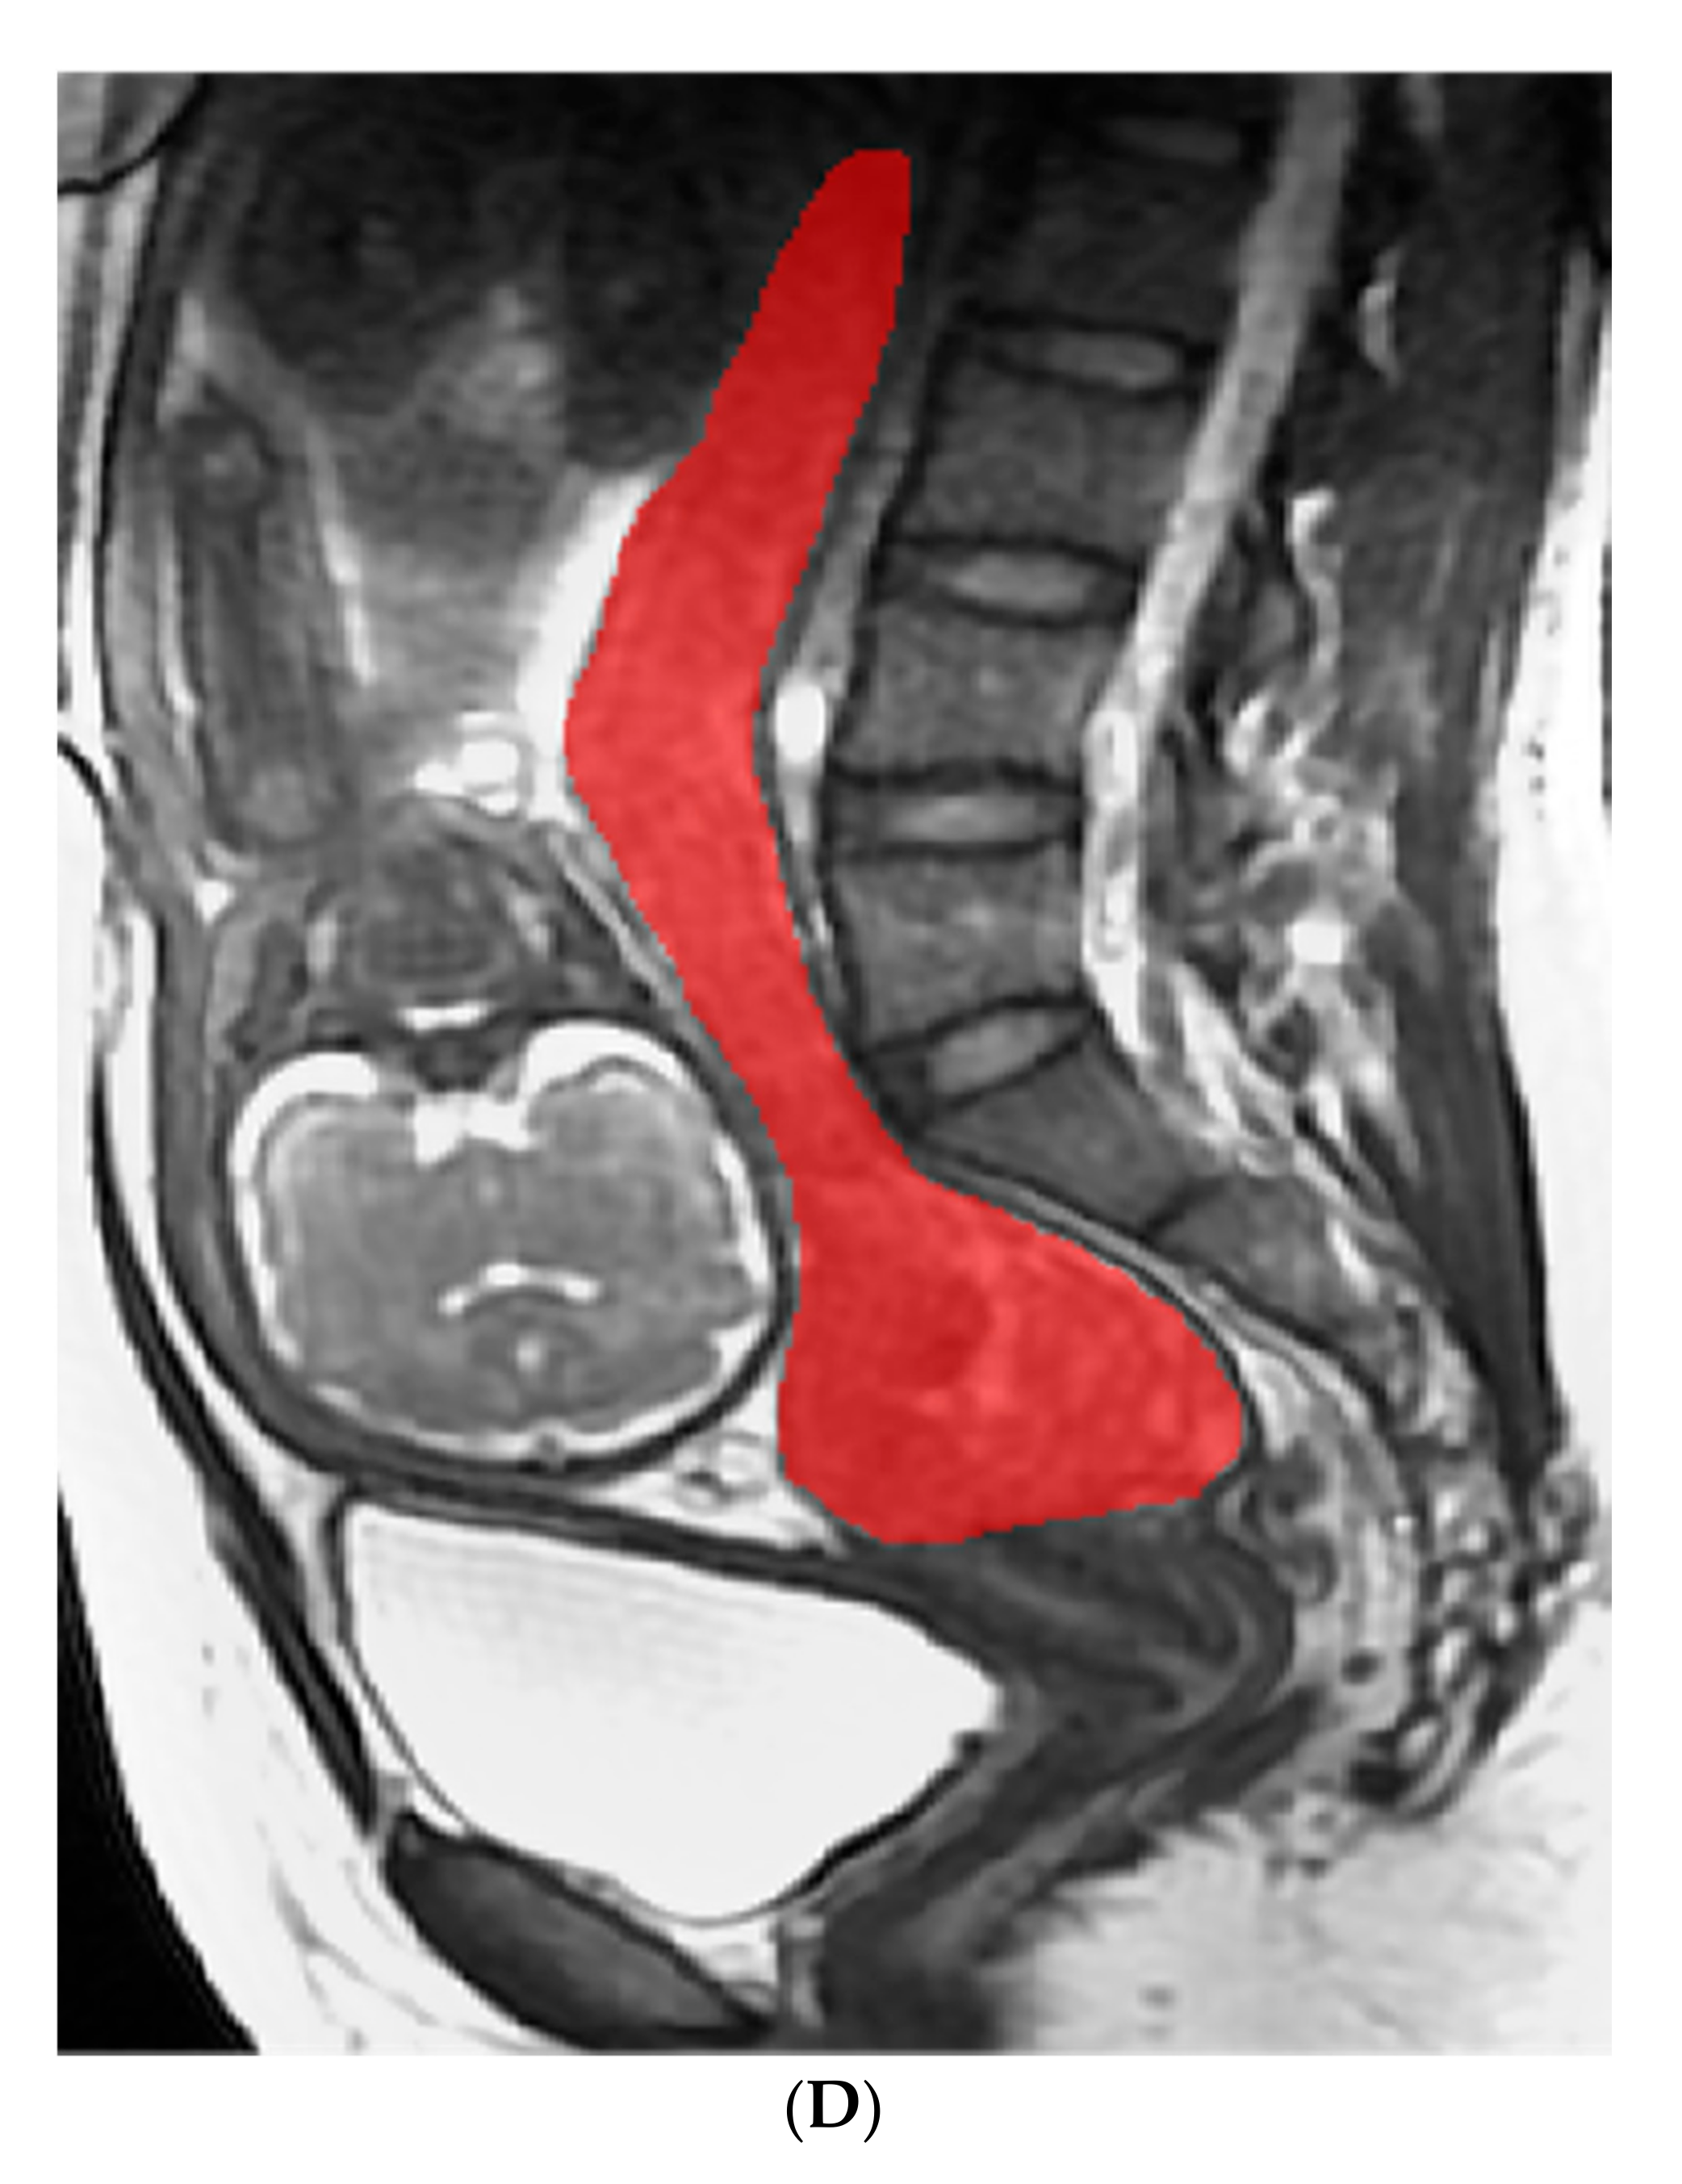

4.4.1. Image Analysis and Segment